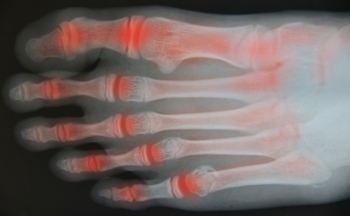

Arthritis in the Toes

Arthritis can occur in any part of the body where joints exist. Since toes have many joints, this is a common place for arthritis to develop. Different types of arthritis can attack the toes, primarily osteoarthritis, rheumatoid arthritis, and gout. If the cartilage wears away between the bones in the toes, they will rub together and inflammation will occur. The big toe is the one most often affected. Past injuries, such as broken or sprained toes, can gradually cause arthritis. Aging, being overweight, and having a family history of arthritis are risk factors for this affliction. Symptoms of toe arthritis include pain, stiffness, and swelling. A clicking, popping, or a grinding noise can also be symptoms. Toe arthritis can cause difficulty with mobility. If you have toe pain, it is suggested that you consult with a podiatrist who can properly diagnose arthritis, and provide correct treatment options.

Arthritic Foot Care

Arthritis is a term that is commonly used to describe joint pain. The condition itself can occur to anyone of any age, race, or gender, and there are over 100 types of it. Nevertheless, arthritis is more commonly found in women compared to men, and it is also more prevalent in those who are overweight. The causes of arthritis vary depending on which type of arthritis you have. Osteoarthritis for example, is often caused by injury, while rheumatoid arthritis is caused by a misdirected immune system.

Symptoms

- Swelling

- Pain

- Stiffness

- Decreased Range of Motion

Arthritic symptoms range in severity, and they may come and go. Some symptoms stay the same for several years but could potentially get worse with time. Severe cases of arthritis can prevent its sufferers from performing daily activities and make walking difficult.

Risk Factors

- Occupation – Occupations requiring repetitive knee movements have been linked to osteoarthritis

- Obesity – Excess weight can contribute to osteoarthritis development

- Infection – Microbial agents can infect the joints and trigger arthritis

- Joint Injuries – Damage to joints may lead to osteoarthritis

- Age – Risk increases with age

- Gender –Most types are more common in women

- Genetics – Arthritis can be hereditary

If you suspect your arthritis is affecting your feet, it is crucial that you see a podiatrist immediately. Your doctor will be able to address your specific case and help you decide which treatment method is best for you.